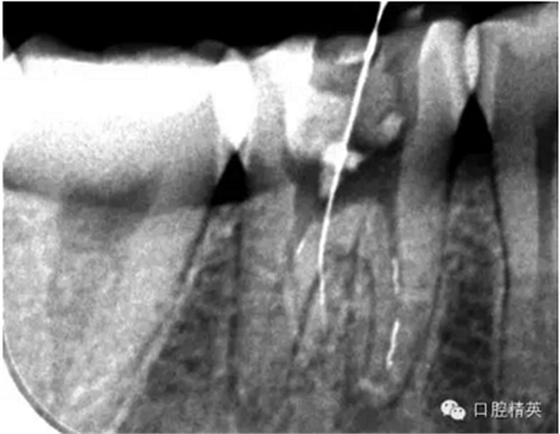

這個(gè)病例是我準(zhǔn)備分根的病例,保留近中根,曾在外院做過干尸長(zhǎng)達(dá)數(shù)十年。8號(hào)挫疏通時(shí)近舌根堵,近頰未找到。在這個(gè)病例中首先要知道是為什么根管難以疏通,首先是長(zhǎng)時(shí)間的干尸,和患者年紀(jì)較大根管逐漸變窄,根管道路可能會(huì)出現(xiàn)堵塞,在這張病例中我能知道的是稍有不慎就會(huì)形成臺(tái)階,從而導(dǎo)致根管堵塞加重,更加難以疏通。

近舌8號(hào)k挫疏通,根尖部彎曲,我花費(fèi)時(shí)間2小時(shí)疏通。我個(gè)人覺得根管能否被疏通,第一個(gè)重要因素是時(shí)間,因?yàn)樽鳛檠荔w牙髓的醫(yī)生,首先就是需要的就是耐心。我個(gè)人覺得耐心是非常重要,因?yàn)楹芏喔鼙皇柰〞r(shí),都是我們快要放棄的時(shí)候。所以我每次都會(huì)安慰自己快好了,快好了,就差一點(diǎn)點(diǎn),在堅(jiān)持一會(huì)兒就好了。可以說(shuō)沒有耐心,想做好牙體牙髓,我個(gè)人覺得很難很難。第二個(gè)就是手法,不知道大家啟用挫是什么挫,一般我個(gè)人認(rèn)為,最好從8號(hào)開始疏通,這樣不容易在狹窄的根管內(nèi)形成臺(tái)階(如果有條件的可以從6號(hào)開始)。